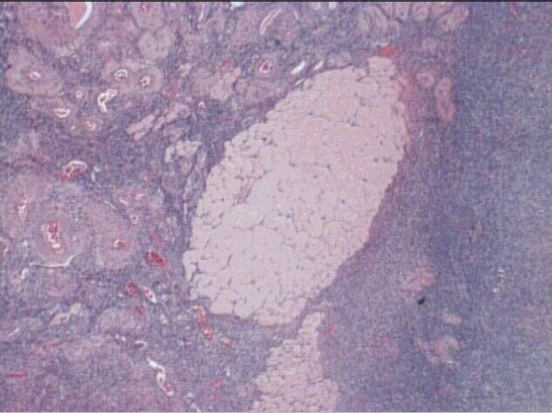

corpus luteum

corpus hemorrhagium

wall of corpus luteum

granulosa lutein cells

theca lutein cells

secrete estrogen and progesterone

lutein cells

thecal lutein cells

corpus albicans